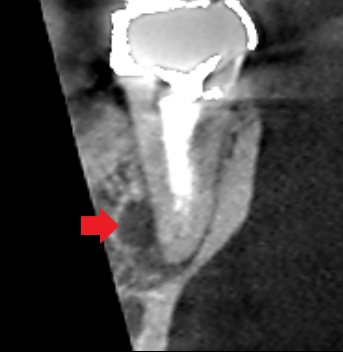

下顎第二大臼歯の冠状断のCT画像です。

矢印の先に膿の影がみられます。膿は根の舌側寄りに拡がっていました。レントゲンでは、根に隠れて膿の本体が把握しにくいケースです。